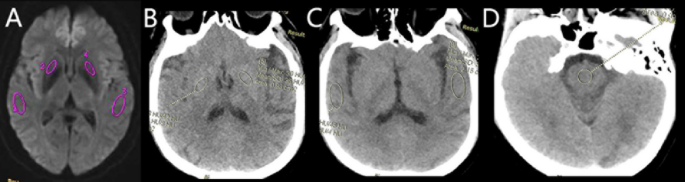

The IVIM and DKI images were transferred to the GE AW4.6 workstation (version 9.4.05, GE Healthcare), and all images were processed and analyzed using a relevant software in the functional kit. The IVIM parameters were calculated using the following Eqs25,26.: Sb/S0 = (1 − f) exp (− bD) + f exp[− b(D*+D)]. This biexponential model was used to calculate ADC, D, D* and f values. The region of interest (ROI) was delineated on the grayscale map with a b-value of 1000 s/mm2. The color-coded parametrical maps of the IVIM were then merged with the grayscale map using the 3D-SynchroView (GE Healthcare). Standardized ROIs were manually drawn on the bilateral temporal lobes, basal ganglia (lenticular nucleus), and on CTP images, the pons (Fig. 1), which served as a relatively stable reference region given its supply from the vertebrobasilar system and typical sparing from MMS27,28. The placement followed a detailed protocol with the following specifics: oval ROIs of ~ 2 cm² were placed in the temporal lobe parenchyma, oval ROIs of ~ 1 cm² were centered on the lenticular nucleus, and circular ROIs of ~ 1 cm² were positioned in the pons, with care taken to avoid large vessels, CSF spaces, and visible infarcts. All measures were operated by two experienced (more than 10 years experience) neuroradiologists. The relative CTP values in our study were defined as the ratios between the absolute CTP values of the temporal lobe or basal ganglia and those of the pons area. The average values were calculated and recorded for statistical analysis. Inter-observer consistency was quantitatively assessed using the intraclass correlation coefficient (ICC).

Schematic illustration of region of interest (ROI) placement. Standardized ROIs were manually drawn on the (A) temporal lobe, (B) basal ganglia (lenticular nucleus), and (C) pons. Panels A and B show ROIs on CT perfusion source images, while panel C shows a corresponding ROI on an IVIM parametric map.